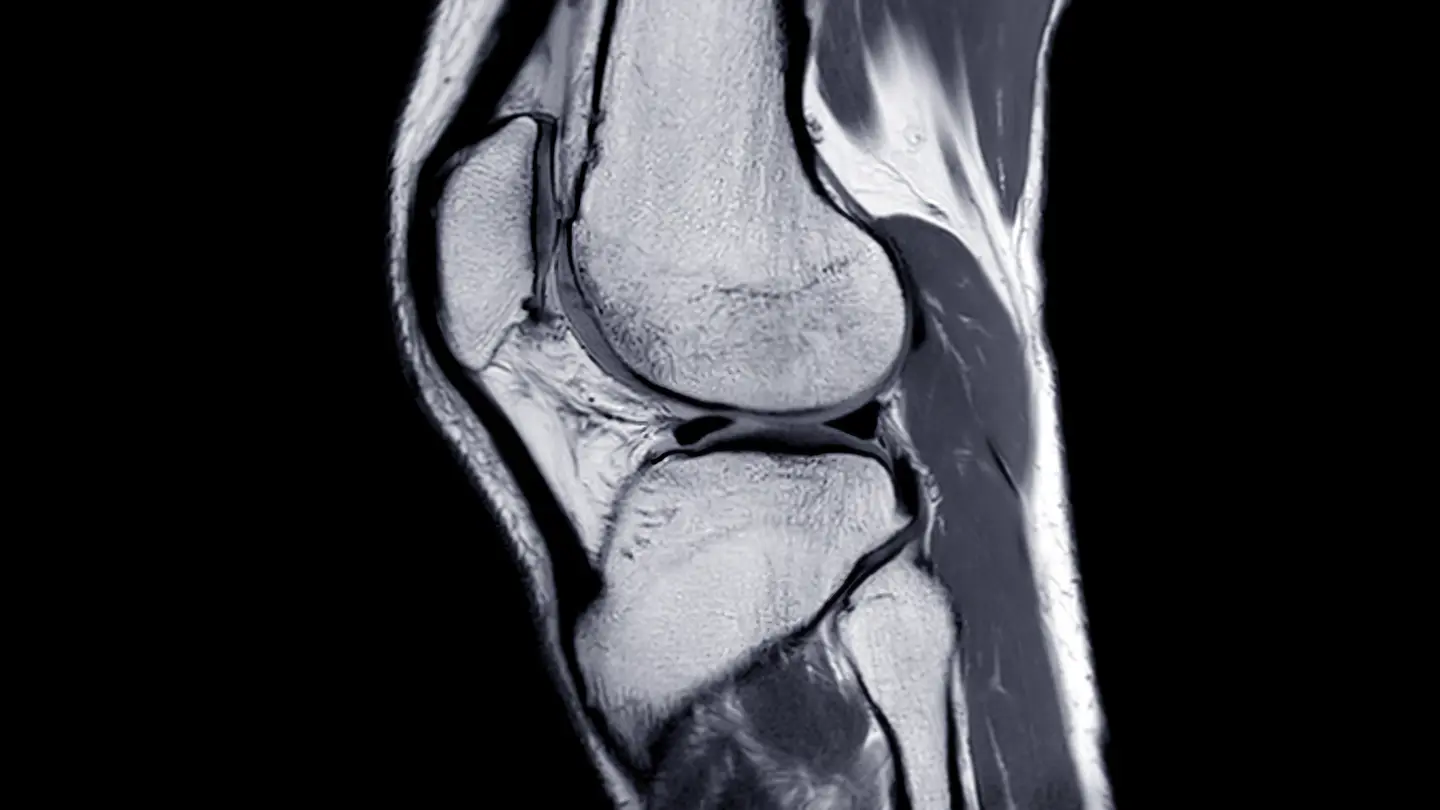

An MR arthrogram combines the use of MRI scanning with a contrast medium to examine the inside of a joint, such as a shoulder, knee, wrist or ankle, and to assess and diagnose injuries and other problems.

MRI Knee Joint

An MR arthrogram scan is used to diagnose and treat joint pain or joint injury related to the knee, shoulder, wrist, elbow, hip or ankle. It provides a clear image of the soft joint tissues.